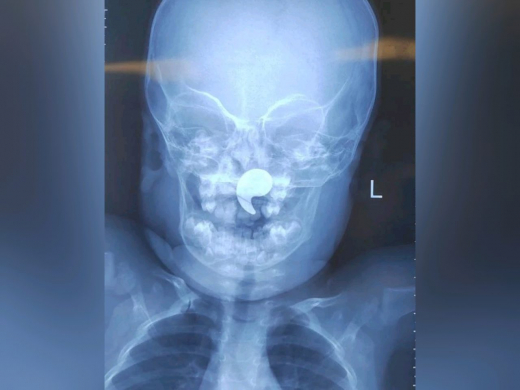

Воронежские врачи спасли полуторагодовалую девочку от удушья — магнит застрял у неё в носоглотке. Об этом сообщила пресс-служба министерства здравоохранения в четверг, 26 марта. Всё началось с того, что девочка играла с магнитом в форме запятой. В какой-то момент он оказался у ребёнка в носу. Мама заметила, что девочка начала давиться, и сама попыталась достать магнит пальцем. Однако это лишь усугубило ситуацию: предмет сместился глубже — в носоглотку. В итоге родители обратились к дежурному ЛОР-врачу. К тому моменту малышка уже жаловалась на боль в горле, отказывалась от еды, а слюнотечение стало активным. Врачи сделали рентген — на снимке отчетливо просматривалось инородное тело. Девочку немедленно госпитализировали в оториноларингологическое отделение ВОДКБ №1. Оперировала ребенка дежурный врач отделения Марина Перепечена. Под общей анестезией, с помощью эндоскопического контроля, она успешно удалила магнит. Уже через сутки девочку выписали домой. Теперь за её здоровьем наблюдает педиатр по месту жительства. Медики подчеркивают: инородные тела в носу — не редкость в детской практике. Но в этом случае магнит оказался в носоглотке. Если бы он попал в гортань или трахею, ребенок мог задохнуться за несколько минут. Врачи просят родителей не пытаться достать инородные тела самостоятельно, а сразу обращаться к врачу.